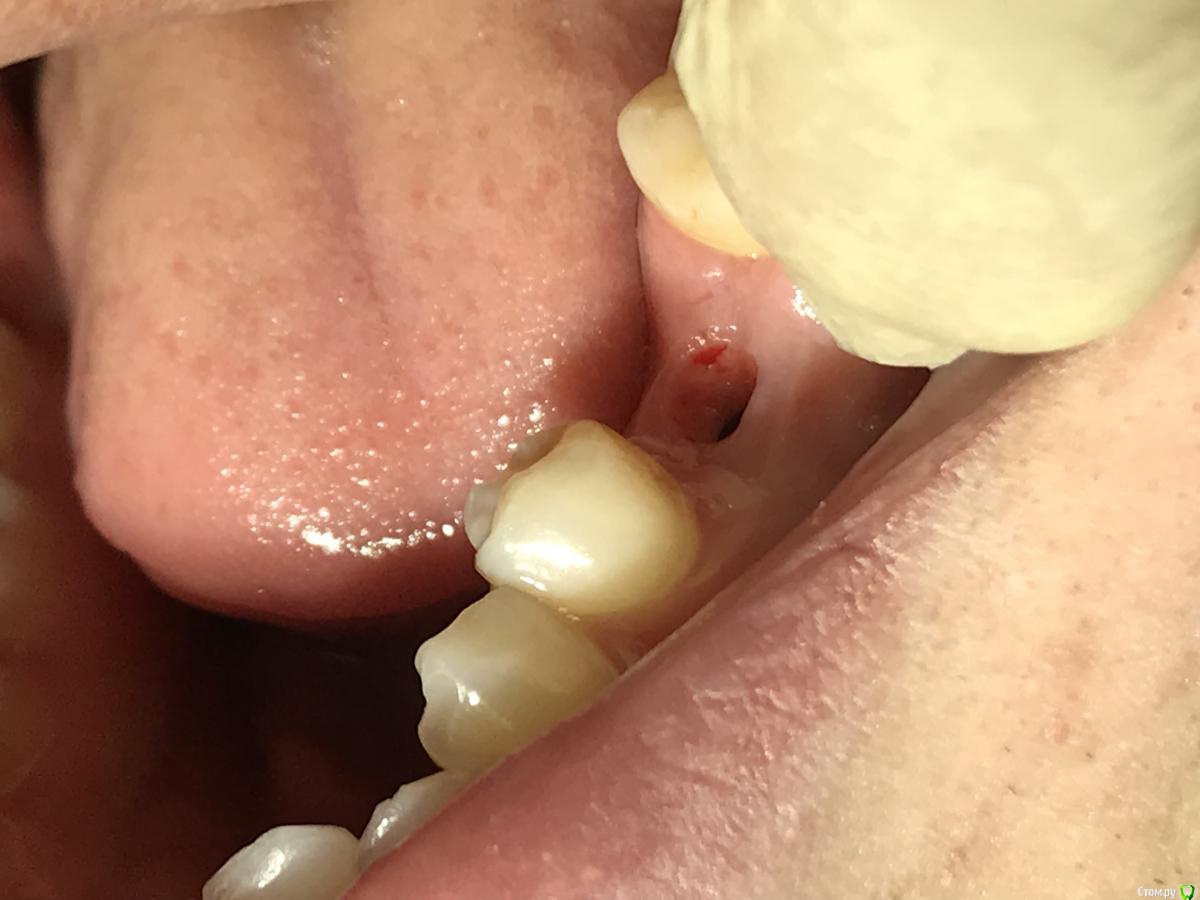

red_butler Опубликовано 22 января, 2020 Поделиться Опубликовано 22 января, 2020 Ранее не было аккаунта , коллега мой закидывал , зарегестрировался сегодняок, фото во рту покажите 1 Ссылка на комментарий

El_cucuy Опубликовано 22 января, 2020 Поделиться Опубликовано 22 января, 2020 ок, фото во рту покажитеХорошо , как раз завтра осмотр Ссылка на комментарий

El_cucuy Опубликовано 26 января, 2020 Поделиться Опубликовано 26 января, 2020 и? Ссылка на комментарий

Дмитрий Л. Опубликовано 26 января, 2020 Поделиться Опубликовано 26 января, 2020 Я бы не подсаживал, вроде 3 мм есть. 1 Ссылка на комментарий

red_butler Опубликовано 26 января, 2020 Поделиться Опубликовано 26 января, 2020 не вижу смысла работать с десной Ссылка на комментарий